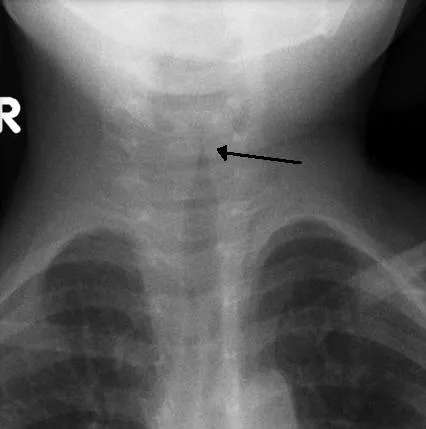

- Croup (Laryngotracheobronchitis): Barking cough, inspiratory stridor, hoarseness (esp. HPIV-1, HPIV-2). 📌 Croup: Steeple sign on neck X-ray.